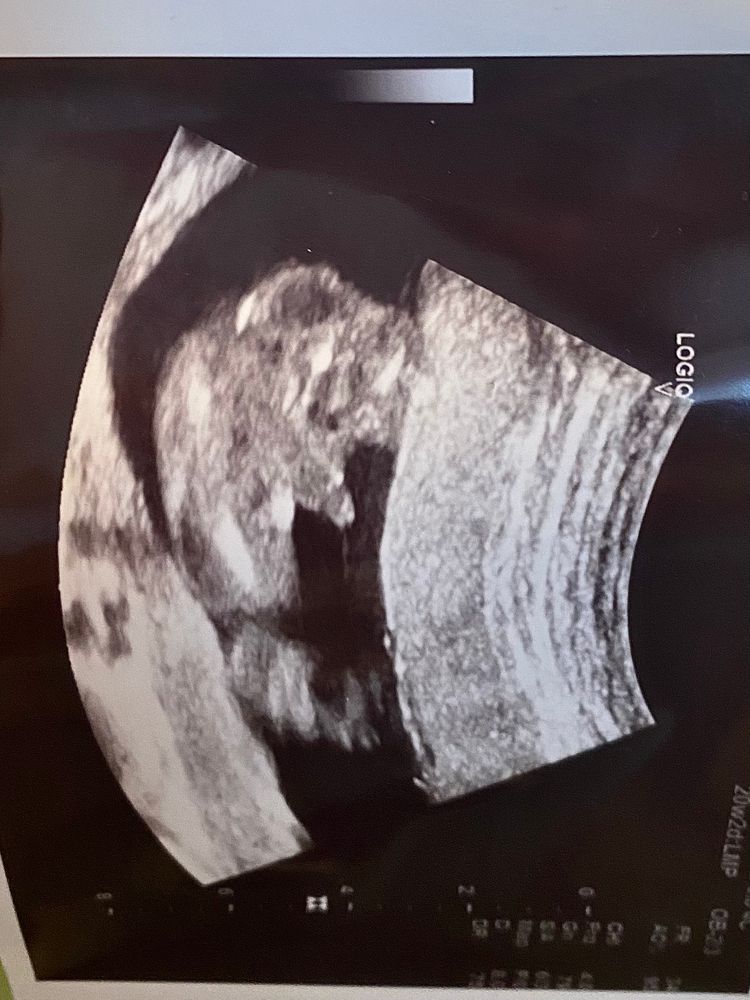

Здравствуйте! Сегодня была на узи, у меня уже 20 недель. Определили, что будет мальчик. Свекровь расстроилась и начала переубеждать. Нет, не подумайте, буду рада любому полу, главное, чтобы ребёнок был здоровым. Но никак не могу понять, ошибся врач или всё-таки и правда мальчишка. Кто разбирается, отпишитесь)

У девочек нет того, что есть у Вашего мальчика)))) Поздравляю с сыночком 🤗🌺

Коннчно паоень.Прекрасно все видно на снимке.Тут 100%без ошибочно пацан💜

на фото прекрасно видно машонку с писюном- тут без вариантов, у меня такое же фото было со вторым.

На Вашем снимке все более чем очевидно)) Мальчуган показал все свои прелести без стеснения 🤗🌺